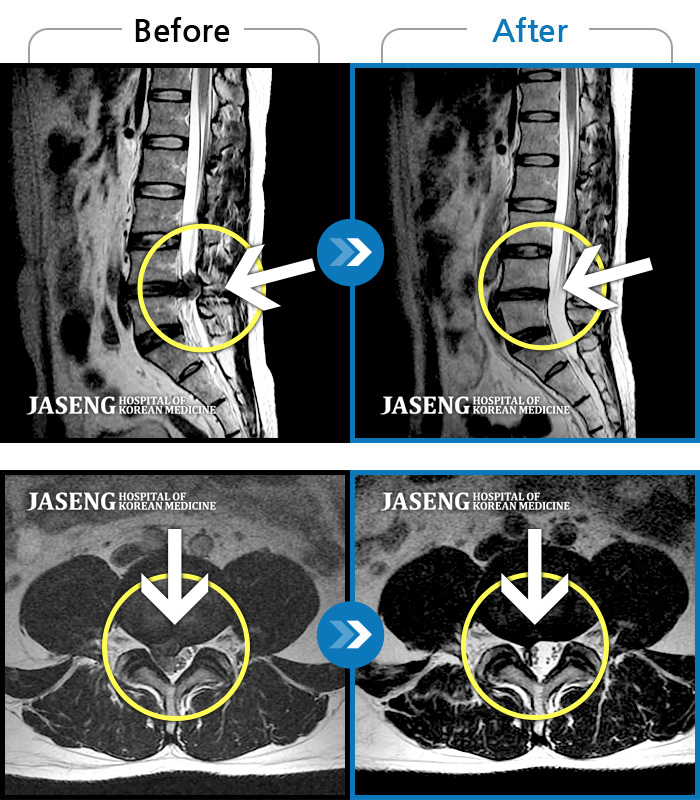

Before

After

앉아 있다가 일어설 때 통증이 증가합니다. 좌측 엉덩이부터 발까지 저립니다.

2023.08.05 ~ 2024.02.28